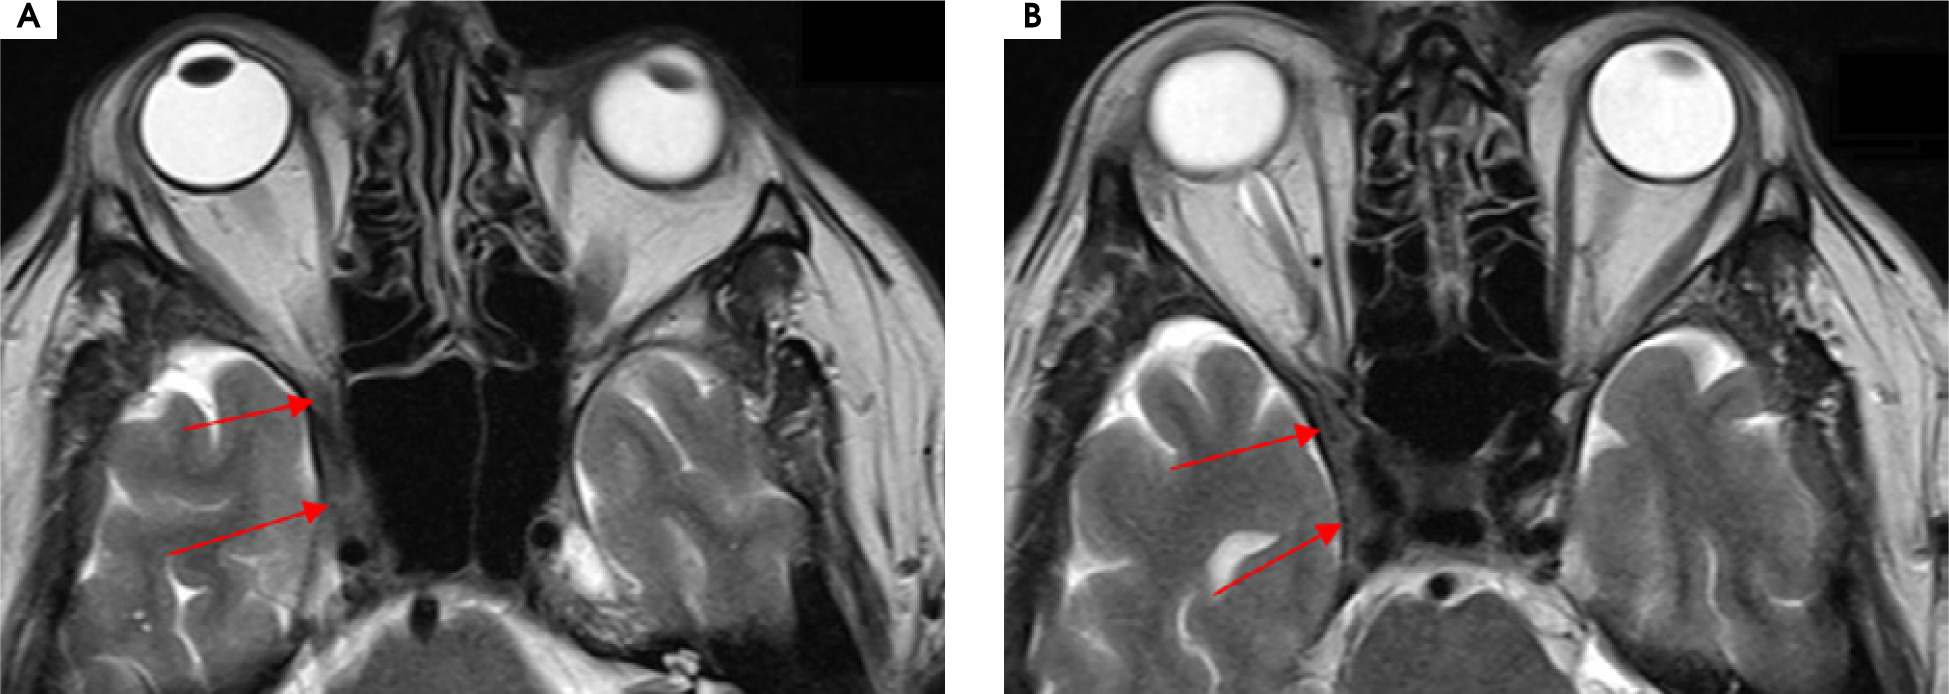

Case 6

A 56-year-old man was admitted to the hospital due to double vision, a problem with the mobility of the right eyeball, and a right-sided headache. The first symptoms were not so obvious due to a prickly headache in the middle of the face, with swelling on its right side. Around 7-8 weeks later typical symptoms appeared, consisting of severe right-sided periorbital headache and ipsilateral eye movement disorder. In the meantime, the patient was treated with antibiotics by a dentist due to suspected peroidontitis. The neurological assessment showed ophthalmoplegia of the right eyeball, ptosis, and exophthalmos. The MRI findings showed asymmetrical reinforcement and thickening up to 6 mm within the cavernous sinus on the right side, laterally directed towards the superior orbital fissure and the top of the orbit. The MRI findings are shown in Figure I and Figure II. Treatment with intravenous steroid was started (1,000 mg of methylprednisolone daily for 7 days), with an improvement of the symptoms, followed by oral steroid of 60 mg of prednisolone in gradually decreasing doses over 36 days. The rapid clinical improvement was observed as shown in Figures III to VI. We also include a video showing the patient’s eye motor functions on the 7th day of the treatment.

Figure I

Patient number 6. Axial MRI T2 sequences showing asymmetrical thickening up to 6 mm within the right cavernous sinus, laterally directed towards the superior orbital fissure and the top of the orbit

Figure II

Patient number 6. Axial MRI T1 sequences with contrast showing asymmetrical reinforcement within the right caver nous sinus